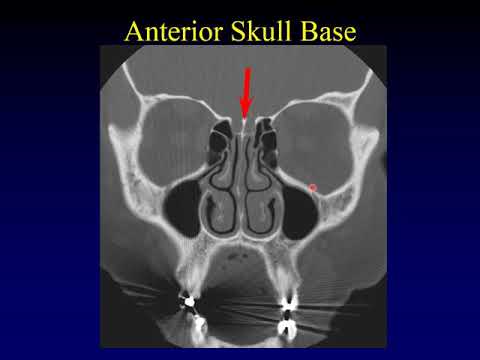

Paranasal Sinus Imaging

Imaging of the Paranasal Sinuses 1